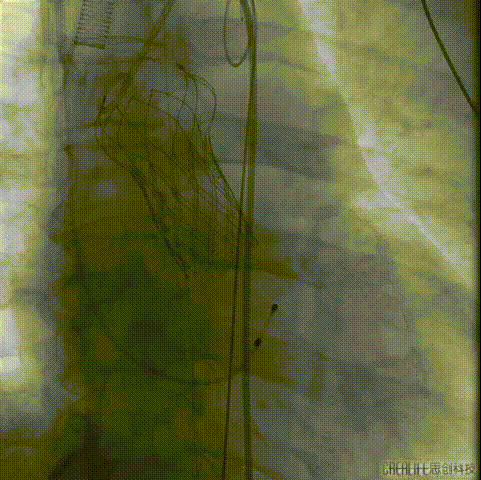

根部造影

定位

第一次释放

第一次释放定位过高

回收

第二次释放

释放至可回收极限